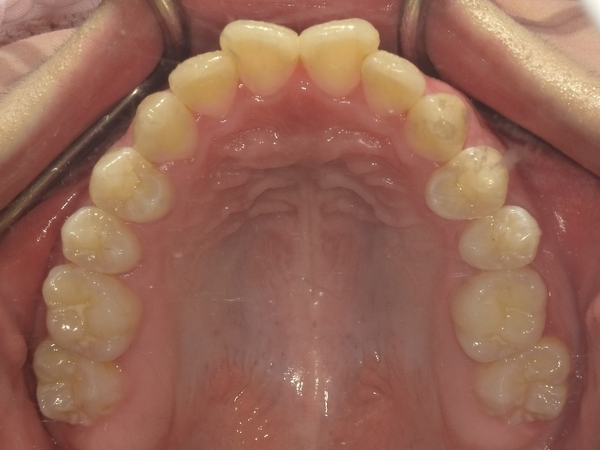

ガタガタとした歯並びや八重歯(叢生)CASE72